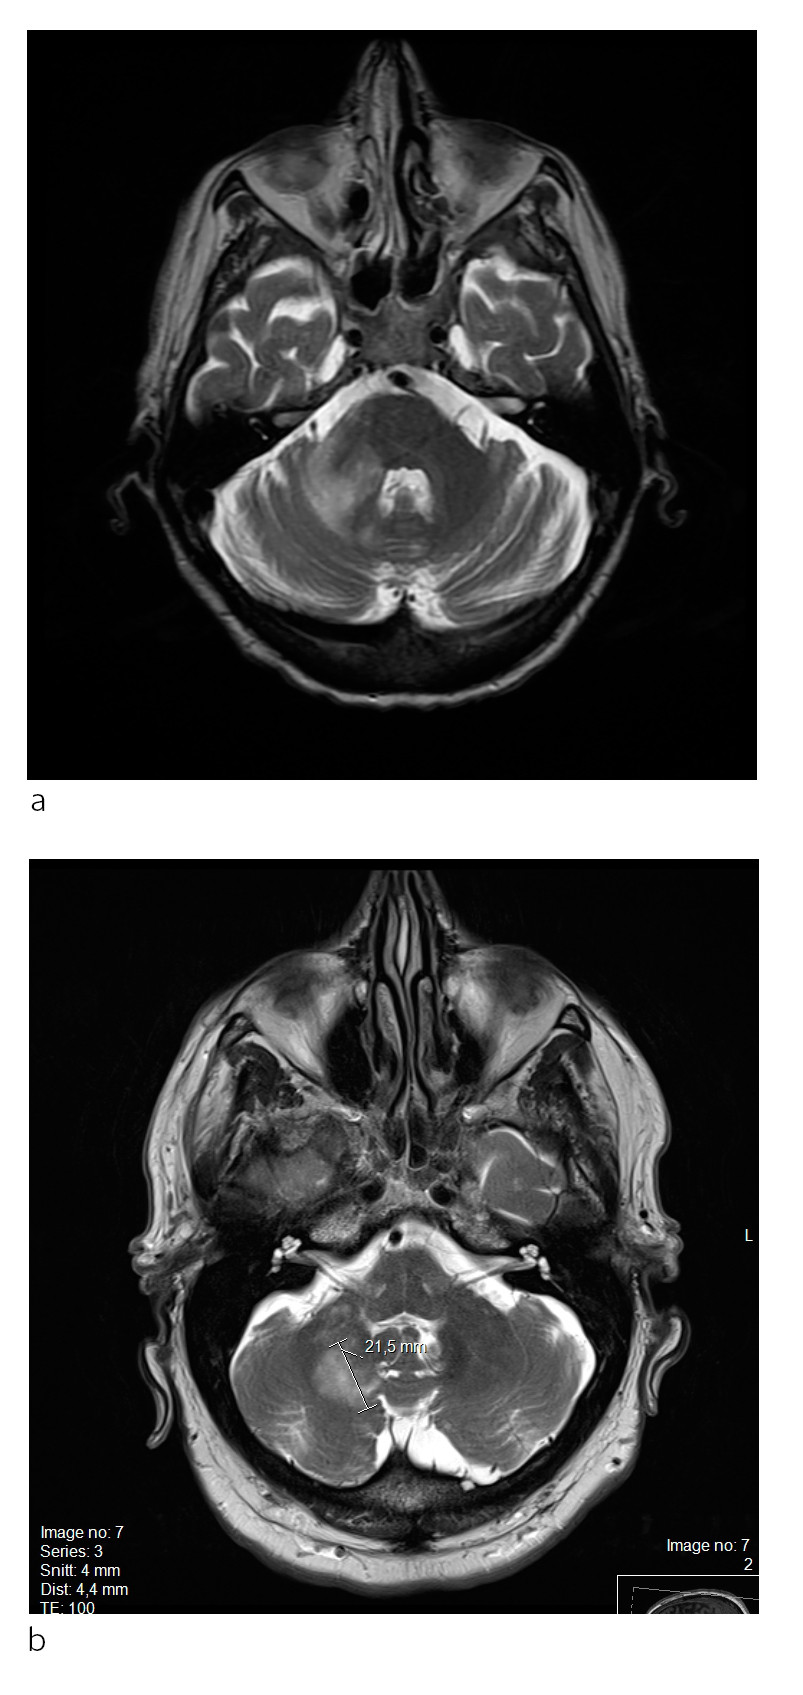

Pasient 2. En kvinne i 50-årene med attakkpreget multippel sklerose var blitt behandlet med natalizumab (Tysabri) over flere år da hun fikk påvist diskrete forandringer på en MR-undersøkelse. Hun hadde da ikke hatt tegn til sykdomsaktivitet på flere år. JCV-antistoff var blitt påvist i serum to år tidligere, men indeks var ikke tilgjengelig på dette tidspunktet. Natalizumab ble seponert, men pasienten utviklet etter hvert likevel ustøhet og dobbeltsyn, og MR-undersøkelse to måneder senere viste betydelig økning av forandringer (fig 2a). Det var en inhomogen høyattenuerende forandring i høyre lillehjernestilk som ikke er lett å skille fra en forandringer ved multippel sklerose. PCR-undersøkelse av JCV-DNA avdekket 1 173 kopier/ml i spinalvæske.

Plasmaferesebehandling ble gitt, men symptomene progredierte. Ny MR-undersøkelse tre uker senere viste kontrastladende lesjoner, forenlig med immunrekonstitusjonsinflammasjonssyndrom (fig 2b). Pasienten fikk høydose metylprednisolon (Solu-medrol), med påfølgende remisjon. Hun ble frisk fra progredierende multifokal leukoencefalopati, men fikk sekvele.